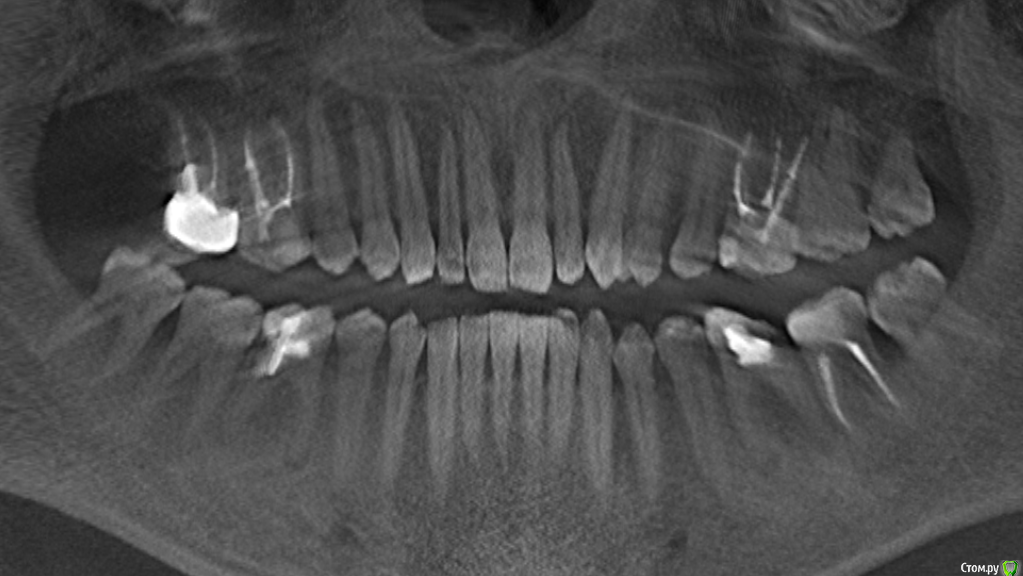

7 зуб с культевой вкладкой. Есть возможность бесплатно перелечить или удалить и поставить имплант (бесплатно). Что выбрать?

Качество снимков не позволяет их интерпретировать

Как сказали выше, качество снимков плохое. Подобие культевой вкладки на снимке еле улавливаю, не исключено что можно перелечить. Если говорить об импланте, нужно сделать КТ.